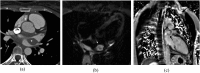

The objectives of this article were: (1) to review common and rare manifestations of systemic and pulmonary Langerhans cell histiocytosis, Rosai-Dorfman disease, Erdheim-Chester disease and juvenile xanthogranuloma; (2) to provide the reader with important pathologic, epidemiologic and clinical features of these diseases. The histiocytoses are a diverse group of diseases which typically manifest with multiorgan involvement. Understanding the pathologic, epidemiologic and clinical features of these entities can help the radiologist suggest an accurate diagnosis of histiocytosis when typical imaging features are encountered.